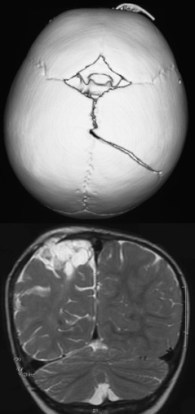

la fracture est le plus souvent pariétale, plus rarement frontale voire orbitaire

lorsque les berges de la fracture sont éloignées de plus de 5 mm, il est hautement probable que la dure-mère sous-jacente soit déchirée

on peut anticiper son développement quand le bilan initial montre unefracture large, une déchirure durale et une contusion sous-jacente

l’IRM est importante pour évaluer l’extension des lésions cérébrales, la rétraction de la dure-mère, l’existence d’un HSD